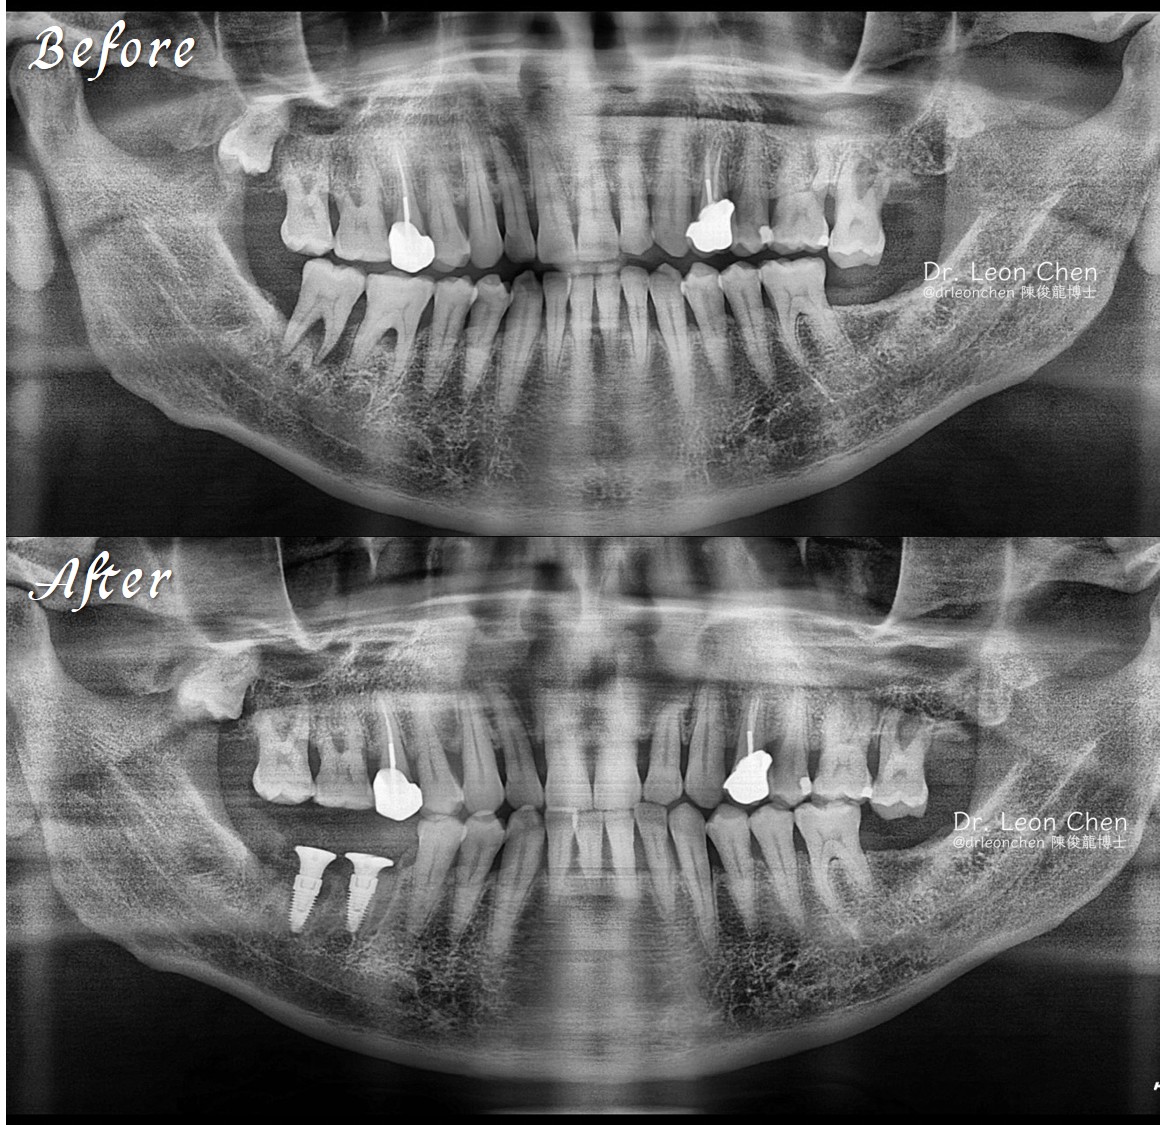

精奈創一鑽植牙系統團隊|糖尿病患者的植牙奇蹟

一位長期患有嚴重糖尿病、控制不佳的病人,過去21年曾到三間診所求診,但因高風險患者而被拒絕。

治療過程中一度緊張到幾乎要暈倒,但在陳博士的專業技術下以及團隊的安撫之下,病人不再害怕,成功完成植牙治療。

陳博士有一套專為高風險患者設計的微創植牙流程,今年也將在微創直牙醫學會上分享這套Protocol。

「陳俊龍博士整套 LEONS Concept 精奈創一鑽植牙」技術,手術少、恢復快,當天就有臨時固定假牙,不需要停藥,適合各類患者,也沒有併發症。